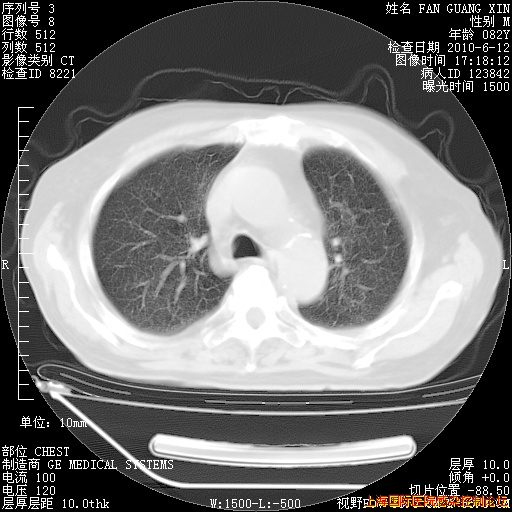

补发6月12日肺部CT肺窗

6月12日肺窗

整整相隔30天的肺部CT好像有所好转啊。甲强龙减量第3天,需要观察体温。

海管,自昨日你和我通完话后,不知您岳父消化道症状有无缓解?体温怎样?阅读7.12日胸部ct,个人认为目前激素治疗是有效的,甲强龙减量是适宜的。因在抗痨治疗,需密切观察肝功、肾功能和血常规。不过,老年、长期住院和大量使用激素,很担心菌群失调发生